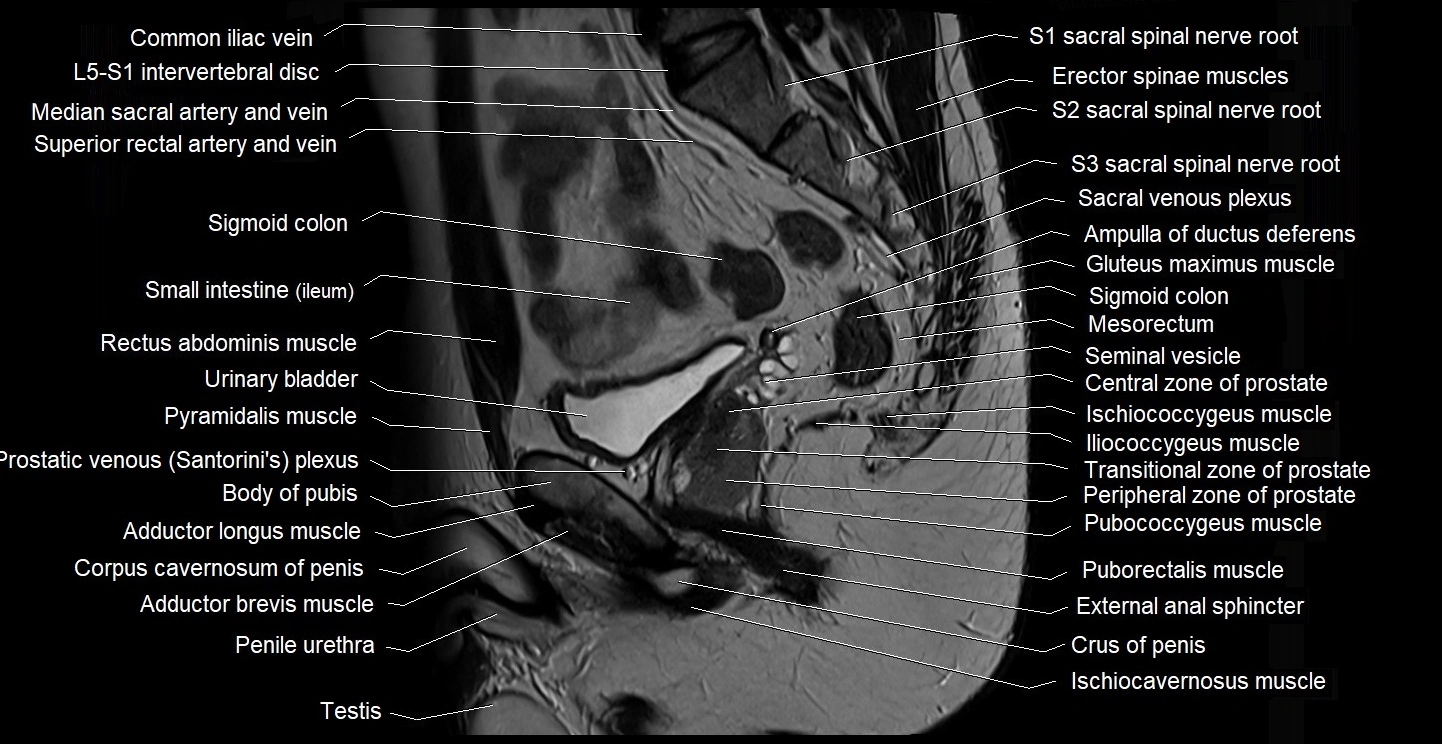

- Central zone of prostate

- Common iliac vein

- Crus of penis

- External anal sphincter

- Gluteus maximus muscle

- Iliococcygeus muscle

- Ischiococcygeus muscle

- L5–S1 Intervertebral disc

- Mesorectum

- Peripheral zone of prostate

- Pubococcygeus muscle

- Puborectalis muscle

- Pyramidal muscle (pyramidalis muscle)

- Rectum

- Seminal vesicle

- Sigmoid colon

- Transitional zone of prostate